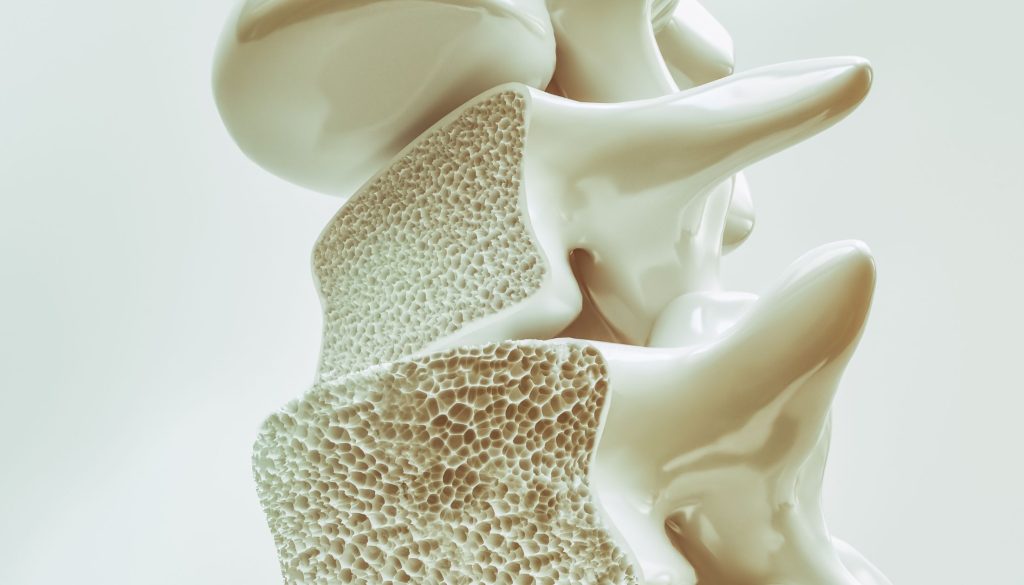

نصائح وتعليمات تثقيفيه بخصوص علاج هشاشة العظام

هشاشة العظام هي حالة مرضية تتسم بضعف وهشاشة العظام، ما يجعلها عرضة للكسر بسهولة. تعتبر هذه المشكلة من القضايا الصحية الشائعة خاصة بين كبار السن، وخصوصاً النساء بعد سن اليأس. يعد التعرف على أساليب الوقاية والعلاج أمراً حيوياً لكل من يعاني من هذا المرض أو المعرضين لخطر الإصابة به.

أعراض هشاشة العظام

في العديد من الأحيان، لا تظهر أعراض واضحة لهشاشة العظام إلا بعد حدوث كسور. مع ذلك، هناك بعض العلامات التي يمكن الانتباه إليها، مثل:

– آلام الظهر الناتجة عن كسور الفقرات.

– فقدان تدريجي للطول.

– وضعية منحنية للجسم.

– كسور تحدث بسهولة مقارنةً بالحالة العادية.

الفحوص والتشخيص

تعتبر تقنية قياس كثافة العظام (DXA) الفحص الأكثر دقة لتشخيص هشاشة العظام. هذا الفحص يحدد كمية المعادن في العظام ويعطي صورة واضحة عن مدى قوتها. قد يُطلب أيضاً إجراء فحوصات أخرى لتحديد مستوى الكالسيوم وفيتامين د في الجسم.